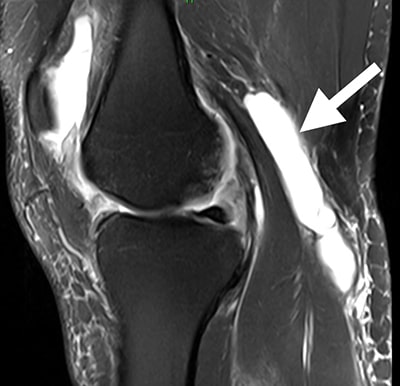

MRI of a Baker's cyst

Esta MRI muestra un área llena de líquido detrás de la rodilla, la ubicación característica del quiste de Baker.